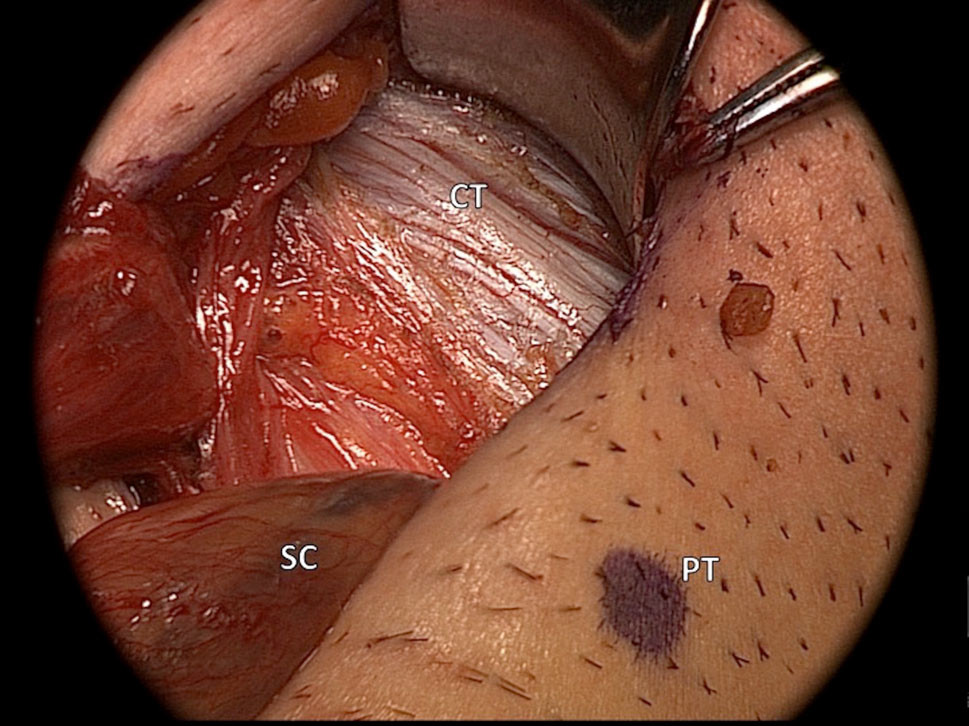

Le cordon spermatique est disséqué au niveau du tubercule pubien et investigué pour exclure la présence d’un sac herniaire (figure 3).

Figure 3 : Le cordon spermatique (SC) est disséqué au niveau du tubercule pubien (PT) et rétracté latéralement exposant le tendon conjoint (CT).